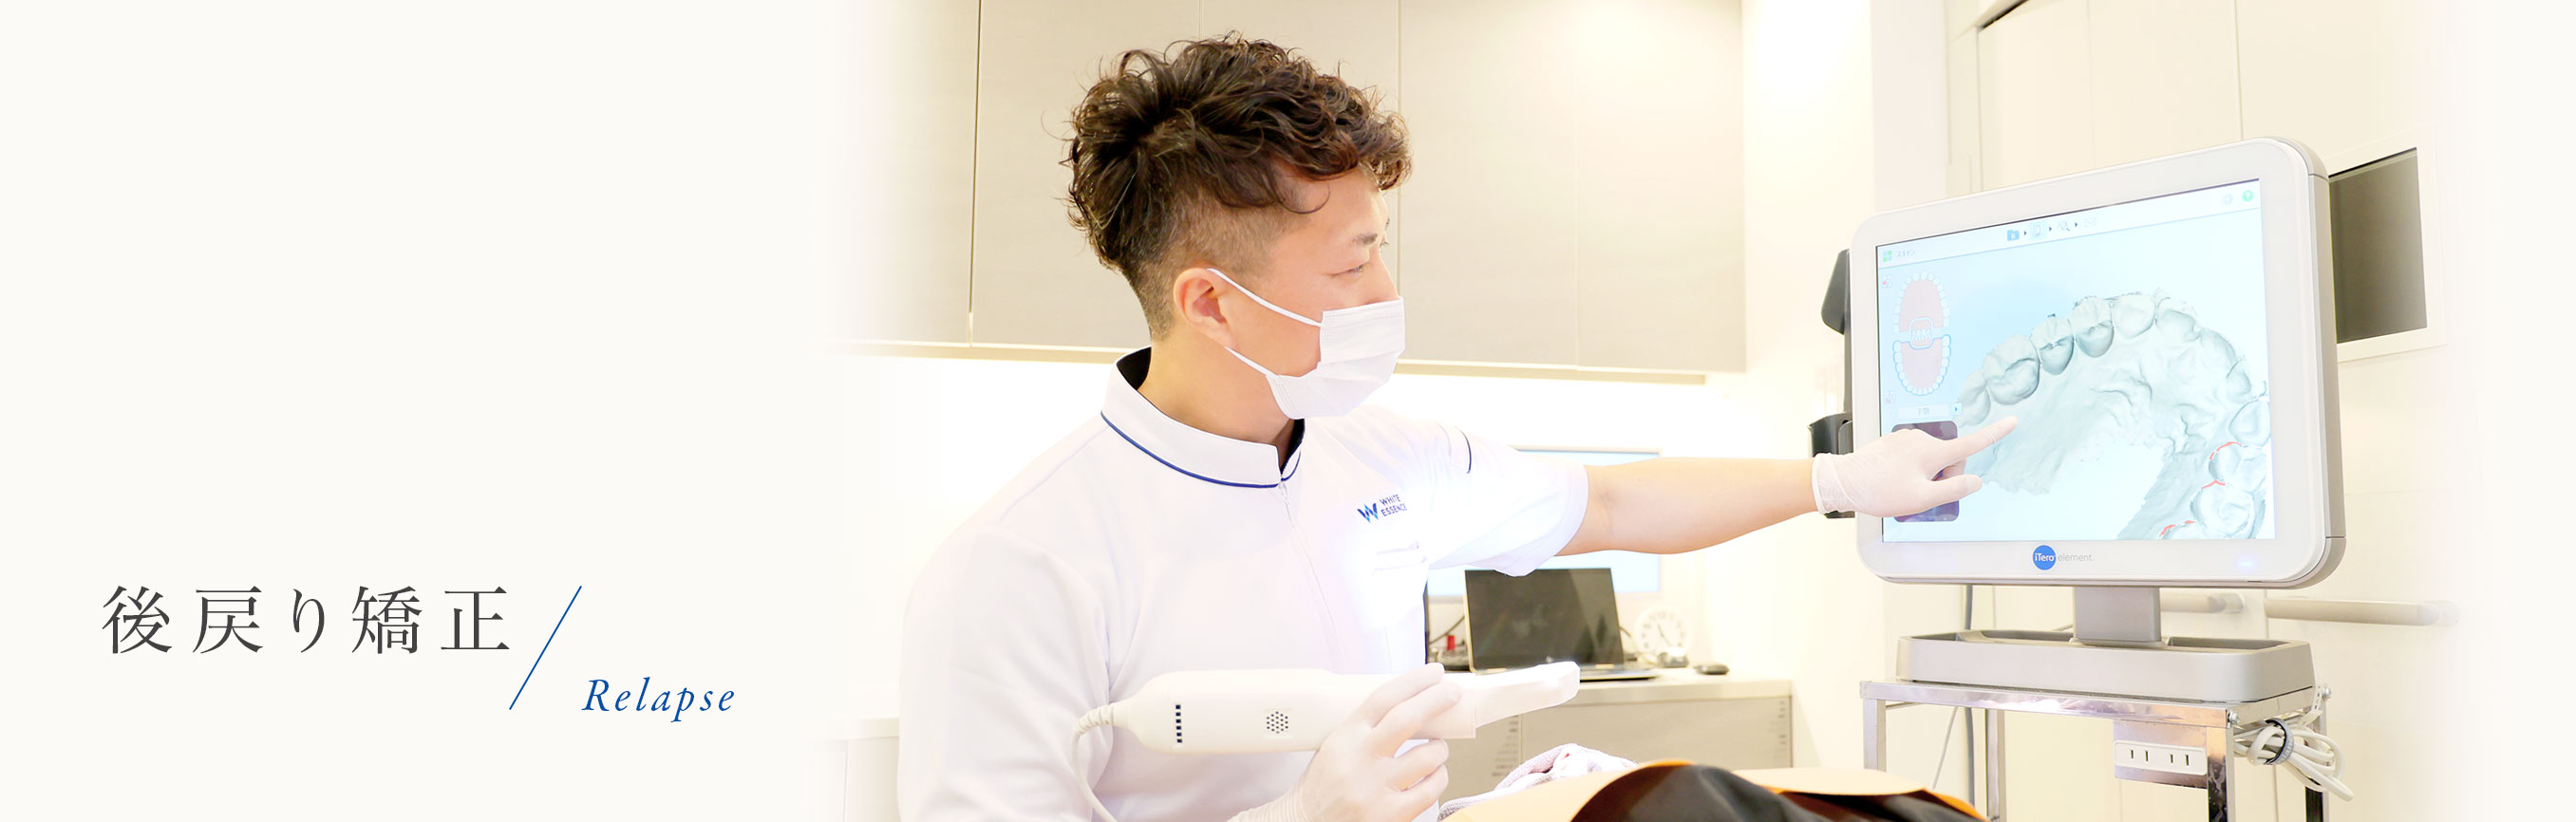

後戻りした歯の「再矯正」

「後戻り」した歯の再矯正プランとは?

その想いをカタチにすべく、当院では、「短期間」かつ「お手頃価格」で後戻り矯正を実施しています。

矯正装置は「マウスピース」を利用します

当院の後戻りの矯正治療は、透明で目立ちにくいマウスピース型矯正装置「インビザライン」を利用します。

マウスピース型矯正装置「インビザライン」

マウスピース矯正のメーカーがたくさんありますが、幅広い症例に適応でき、世界NO.1シェアを獲得しているインビザラインを採用しています。